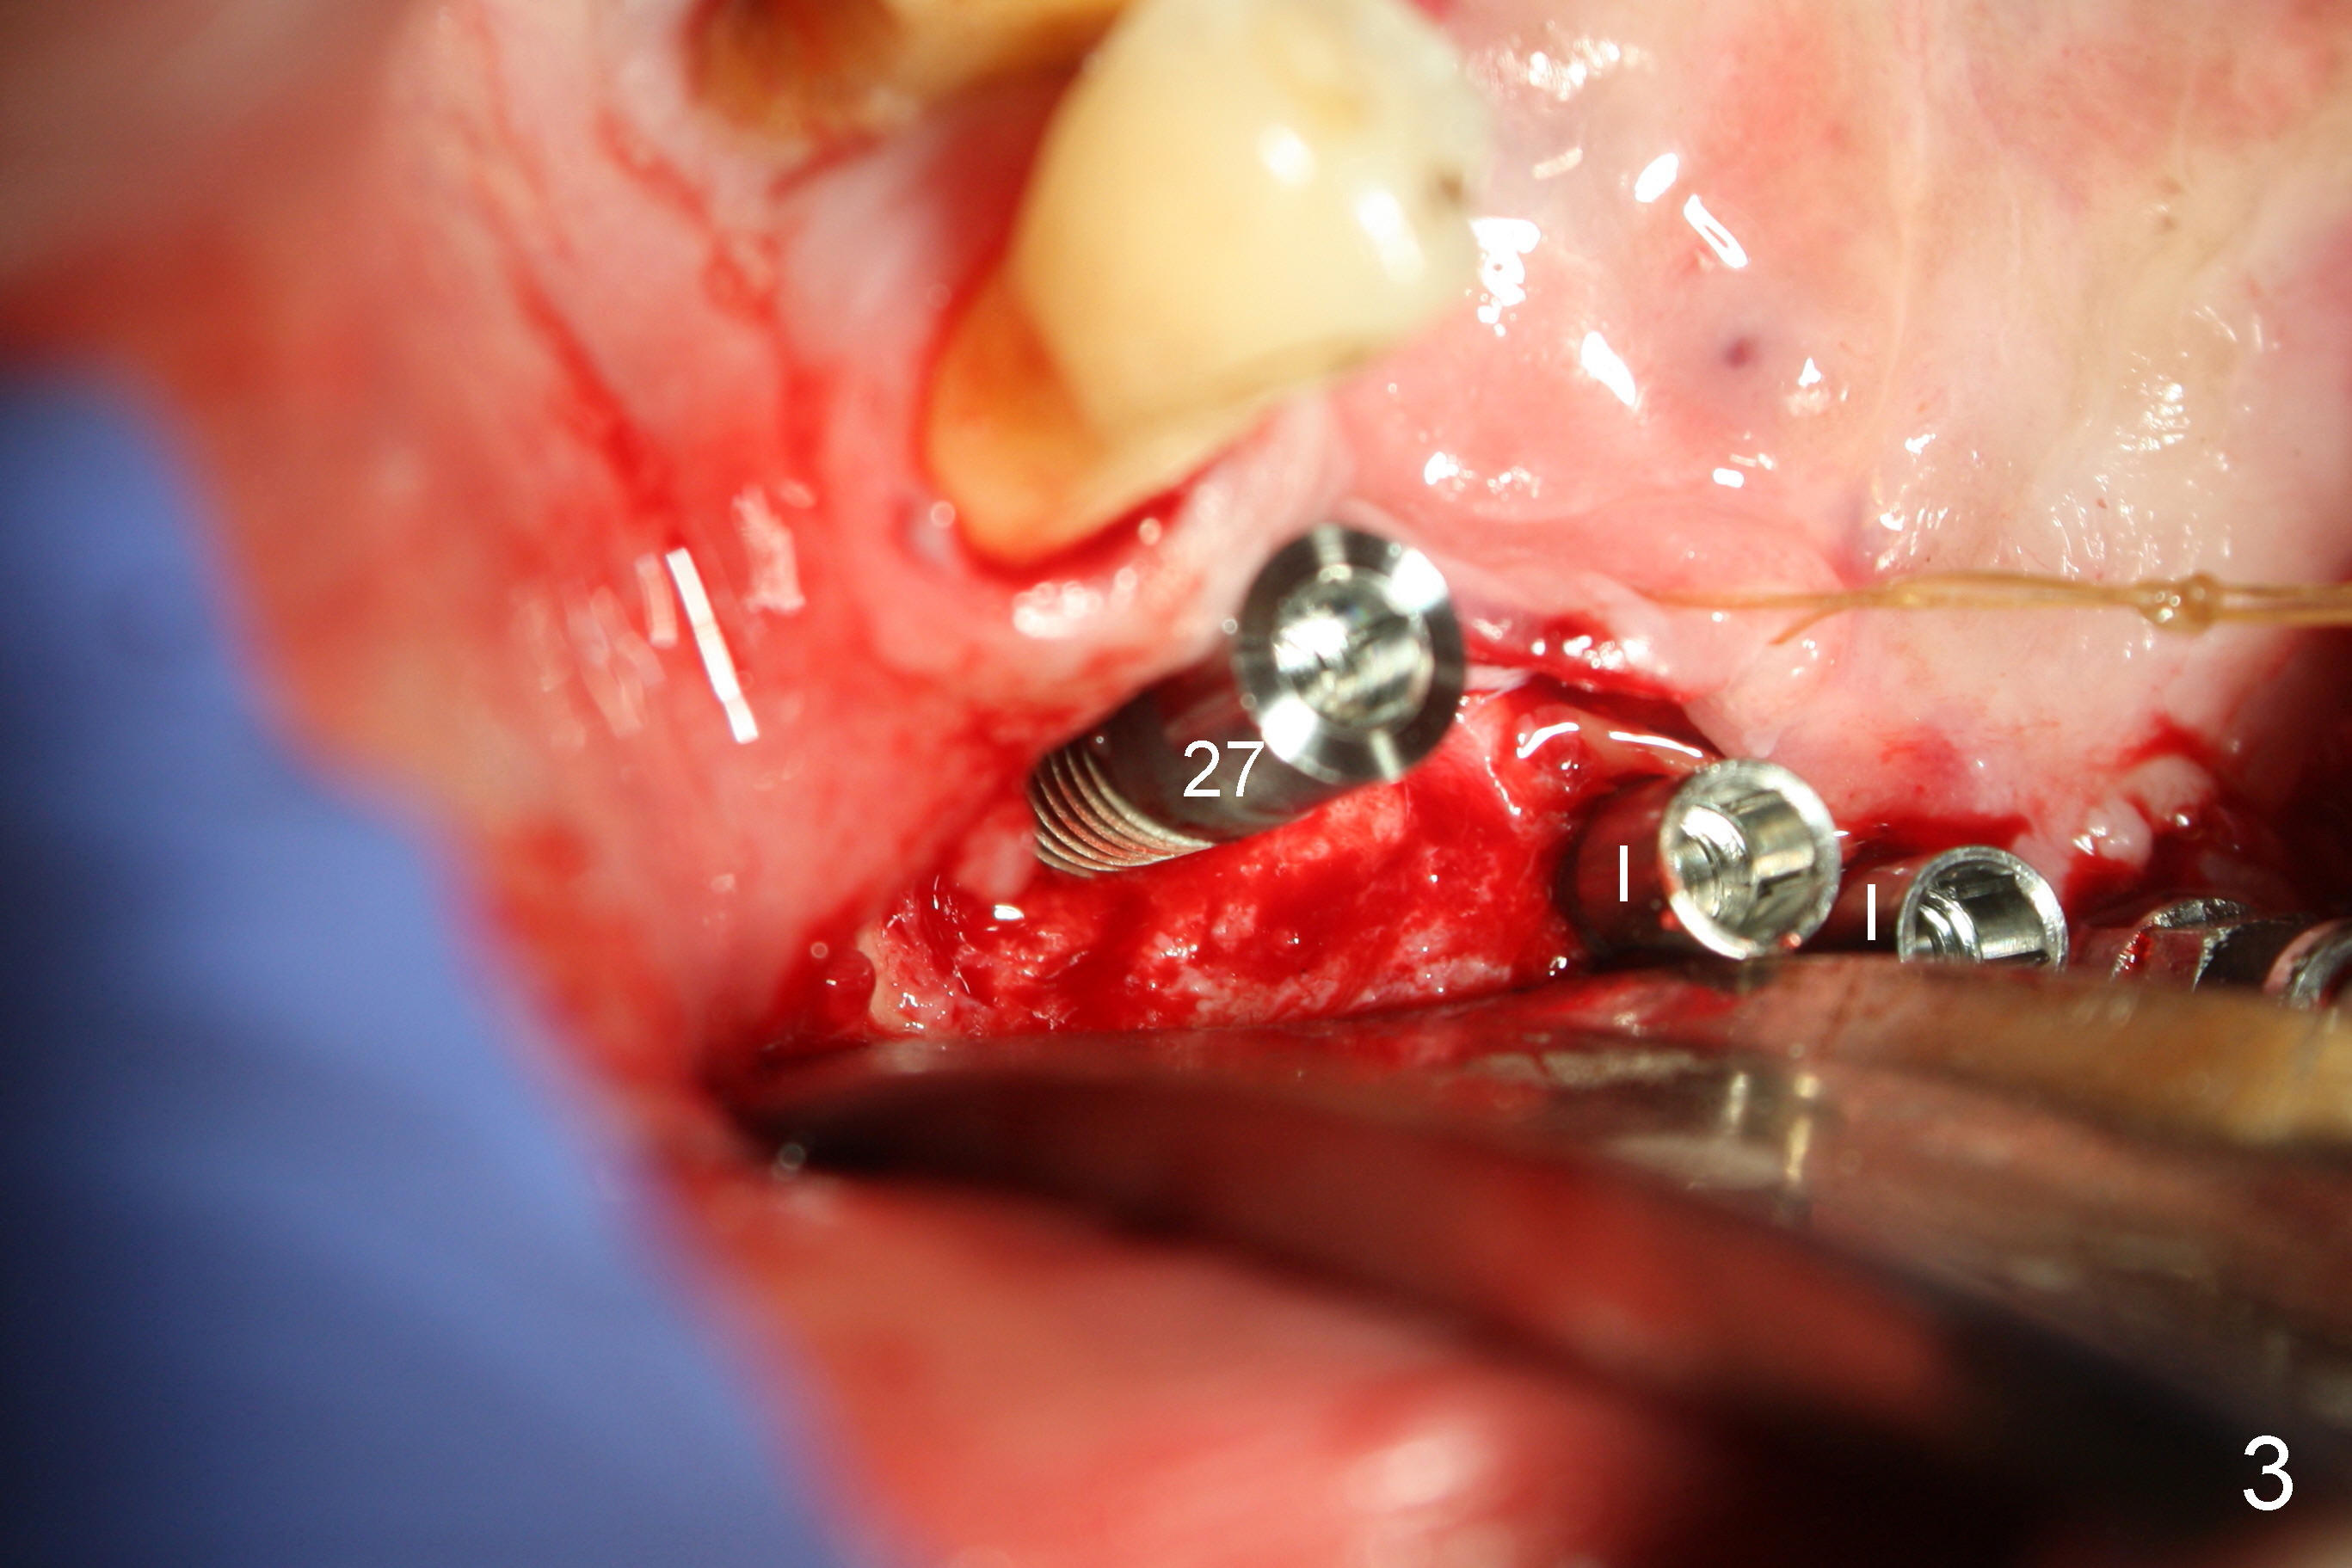

Treatment plan of the 1st surgery consists of extraction of #20 and 21/immediate implants (Fig.1 x), and placement of 4 implants between #22 and 27. Osteotomy at the extraction sites without incision (close surgery) turns out to be difficult; it appears to encroach the inferior alveolar nerve and mental loop. The sockets are subsequently bone grafted (Fig.2 *: mixture of autogenous bone and allograft). Incision is the made in the incisor edentulous region for placement of 3.5x17 mm implants (Fig.3 I).

Osteotomy is initiated through the gingiva of the healing sockets at the sites of #22 and 27 (Fig.1) with difficulty (close surgery). The incisor crest incision is extended distal to the canine areas; an accessory oblique incision is supplemented to facilitate implantation (#22: 5x14 mm; #27: 4.5x17 mm) and expose the buccal defects (Fig.3,4, open surgery). The defects are grafted (Fig.5) and covered by collagen membrane (Fig.6). The incisions are closed and abutments are placed for immediate provisional (Fig.7).